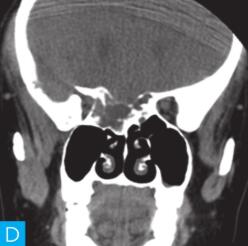

CT检查:检查设备为16层CT,病人采取仰卧位,扫描范围包括双侧鼻窦。扫描参数:层厚2.5mm,120kV,150mA,矩阵512×512。观察图像:软组织窗窗宽300HU,窗位60HU;骨窗窗宽2000HU,窗位400HU,见图1。

图1 鼻窦CT:A. CT横断面(骨窗);B. CT横断面(软组织窗);C. CT冠状面(骨窗);D. CT冠状面(软组织窗)

CT平扫示后组筛窦区见轻度膨胀性骨质破坏,内部密度混杂,可见斑片状、分隔状骨质密度影,部分呈磨玻璃改变,病变边缘清晰,可见薄层骨壳及硬化边。

发现病变较为容易,主要分析其病变的良恶性。本病例基本征象为病变区域呈轻度膨胀性骨质破坏,邻近骨质呈轻度压迫性骨质吸收,边缘可见硬化边,提示病变慢性进展过程,病变内部密度欠均匀,以软组织密度以及磨玻璃样高密度为主。

本病例CT上特点为轻度膨胀性压迫性骨质吸收,边缘骨质见硬化边,呈薄层骨壳表现,提示肿瘤良性可能;病变内部密度不均匀,可见骨性间隔及斑片状磨玻璃骨性密度影,提示病变可能为骨纤维源性肿瘤或肿瘤样病变。

本病例定位不难,病变主体位于双侧后组筛窦区域。病变区呈轻度膨胀性骨质破坏,内部以软组织密度成分为主,正常筛窦的骨性间隔破坏消失,边缘骨质硬化,提示病变进展速度相对缓慢,对于病变的良恶性定性有一定价值,考虑病变为良性病变。

除此之外,我们需注意病变内部变异出现了大片状磨玻璃样骨性高密度影;一般来说,骨内病变出现磨玻璃密度,极大可能提示病变可能为骨纤维源性肿瘤,其病理上多数是由于纤维化骨不完全所致。需要了解的是,发生于颌面骨的骨纤维源性良性肿瘤或肿瘤样病变较为常见的是骨化性纤维瘤和骨纤维异常增殖症,两者在病理水平较难鉴别,但在影像学表现上有各自的特点。骨化性纤维瘤主要发生于颌面骨,一般以单骨受累为主,因组织分化不同,内部成分多混杂,可出现软组织密度、囊性密度、磨玻璃密度以及骨性密度等;另外骨化性纤维瘤外周一般会有较为明显的骨壳包绕,也是诊断要点。而发生于颌面骨的骨纤维异常增殖症,一般呈多骨受累,同时骨质膨胀变形较骨化性纤维瘤更为明显。

与骨化性纤维瘤比较,骨纤维异常增殖症骨质密度相对均匀,主要以磨玻璃样密度为主,外周出现骨壳的概率也较小。结合本病例,病变主要以单骨受累为主,呈轻度膨胀改变,其内部密度不均伴有磨玻璃密度改变,边缘呈薄层骨壳样改变,应该考虑到骨化性纤维瘤的诊断。